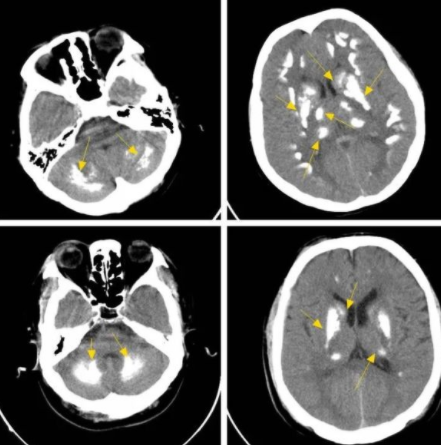

结节在医学不同专业、不同部位的解释都不一样,这里我们以肺结节为例,结节指的是边界清楚、影像不透明、直径小于或等于 3mm、周围为含气肺组织所包绕的病变。通常可分为实性与非实性结节。发现结节不等于就有恶性肿瘤存在,还需进一步鉴别诊断按是否有恶性肿瘤、良性病变、感染病变以及非感染性病变等。直径小于4 mm 的孤立微小结节是原发性肺癌的机率小于1%,反之,直径为8 mm 的小结节是原发性肺癌的机率则上升10%~20%。毛玻璃样密度定义为: 在高分辨力 CT 上呈模糊的致密影而其中仍能见到支气管结构或肺血管,毛玻璃密度影的原因比较多,例如炎性病变,肺泡出血以及肿瘤性病变。按影像学表现分为纯毛玻璃密度影和混合毛玻璃密度影,在早年的一些文献报道中,单纯毛玻璃结节中肺癌患病率为18%,混合毛玻璃结节中肺癌患病率为63%,因此混合毛玻璃结节需要更加积极处理。临床上指的是病理性钙化,除骨和牙齿外,在机体的其他组织发生钙盐沉着的现象,一是代谢后的产物、 二是感染与发炎后的痕迹、 三是肿瘤发展过程中因坏死及炎性反应而形成的组织变化。

图示 脑部钙化情况

基本上,钙化大多没有任何症状,和肿瘤也无太大关联。部分脏器,如乳腺、肾脏和胰腺的肿瘤常发生钙化,且钙化形态和分布对评价恶性肿瘤存在的可能性有较大意义,以上部位尤其是乳腺的钙化灶通常需要做进一步评价。